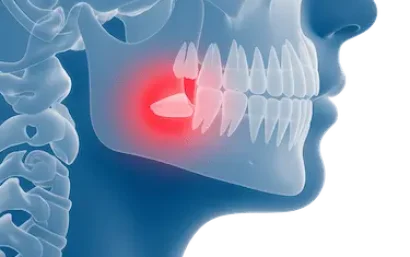

Una vez que la pulpa del diente se ha lesionado, esta se inflama por el contacto con bacterias procedentes de caries o la propia saliva, infectando el interior del diente.

Si no se trata a tiempo, la infección se puede propagar hasta la punta de la raíz para formar un absceso, un granuloma (pequeñas protuberancias rojas que sangran fácilmente) o incluso un quiste.

Cuando la infección en un diente se expande dentro del hueso, se produce una inflamación que provoca una sensación de movilidad del diente y dolor en la muela o diente. El paciente puede presentar ganglios inflamados y hasta fiebre.